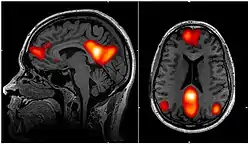

Static connectivity

One of the first methods ever used to analyze DFC was pattern analysis of fMRI images to show that there are patterns of activation in spatially separated brain regions that tend to have synchronous activity. It has become clear that there is a spatial and temporal periodicity in the brain that probably reflects some of the constant processes of the brain. Repeating patterns of network information have been suggested to account for 25–50% of the variance in fMRI BOLD data.[7][13] These patterns of activity have primarily been seen in rats as a propagating wave of synchronized activity along the cortex. These waves have also been shown to be related to underlying neural activity, and has been shown to be present in humans as well as rats.[7]

fMRI is the primary means of investigating DFC. This presents unique challenges because fMRI has fairly low temporal resolution, typically 0.5 Hz, and is only an indirect measure of neural activity. The indirect nature of fMRI analysis suggests that validation is needed to show that findings from fMRI are actually relevant and reflective of neural activity.